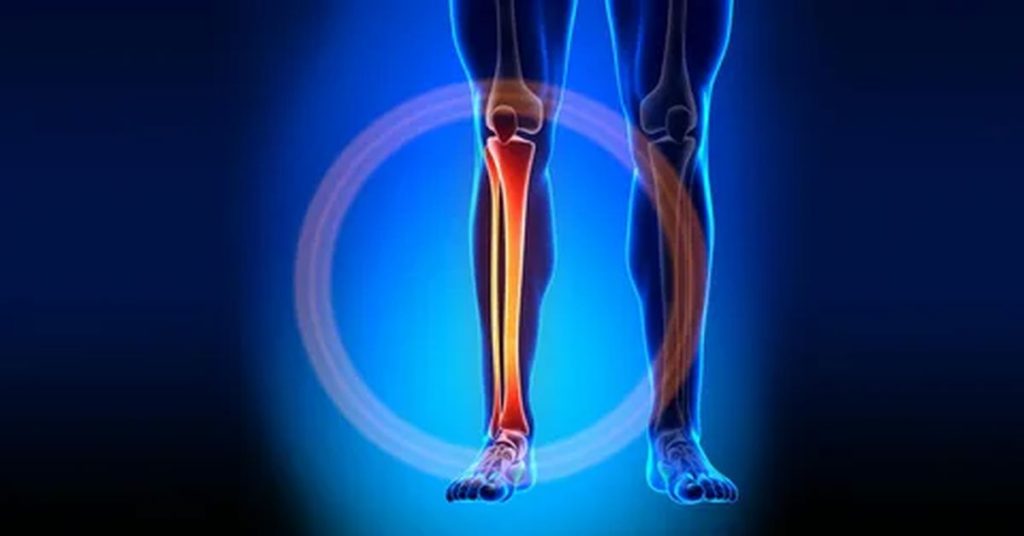

Kaval kemiği kırığı, genellikle darbeler, spor yaralanmaları veya kazalar sonucu oluşur. Tedavi, kırığın türüne göre değişir. Hafif kırıklarda alçı veya atel ile sabitleme yapılırken, daha karmaşık vakalarda cerrahi müdahale gerekebilir. Cerrahi işlemde, kemikler doğru pozisyonda sabitlenir. Ameliyat sonrası fiziksel terapi önemlidir. Kaval kemiği kırığı tedavisi, uygun yöntemlerle başarılı sonuçlar verir ve hastaların iyileşmesini hızlandırır.

Kaval kemiği kırığı, bacakta ciddi bir yaralanmadır. Genellikle düşme, trafik kazası veya spor yaralanmalarından kaynaklanır. Bu tür kırıklarda, kemiğin düzgün iyileşmesi için doğru tedavi büyük önem taşır. Erken müdahale, iyileşme sürecini hızlandırabilir ve kalıcı hasarları önleyebilir.

Kaval kemiği kırığı, bacakta meydana gelen ciddi kırıkların tedavisinde uygulanır. Genellikle düşme, trafik kazası veya spor aktiviteleri sırasında oluşan bu kırıklar, bacağın fonksiyonlarını önemli ölçüde etkiler. Kaval kemiği, vücudun en büyük kemiklerinden biri olduğu için, kırıldığında ciddi ağrılar yaşanabilir. Bu tür bir kırık, doğru tedavi edilmediği takdirde kalıcı sakatlıklara yol açabilir. Sonuç olarak, kaval kemiği kırığı tedavisi, bu tür ciddi durumlarda doğru ve hızlı müdahaleyle hastaların iyileşmesini sağlar.

Kaval kemiği kırığı, bacakta ciddi bir yaralanmadır. Genellikle düşme, trafik kazası veya spor yaralanmaları sonucu meydana gelir. Bu kırıklar, bacağın hareket kabiliyetini kısıtlar ve tedavi edilmediği takdirde kalıcı sakatlıklara yol açabilir. Kaval kemiği kırığının tedavi edilmesi, kemiklerin düzgün bir şekilde iyileşmesi için önemlidir.